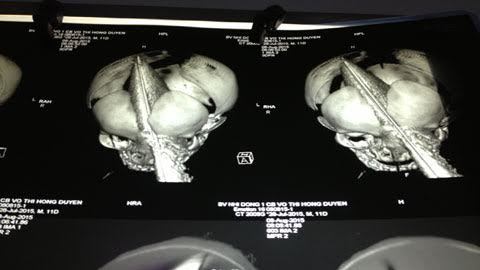

![]() |

| Phim chụp đánh giá tổn thương do dao đâm xuyên sọ bé sơ sinh |

Đường đi vào của lưỡi dao bắt đầu từ giữa trán, đi vào hốc mắt trái, xuyên qua sọ, mũi dao trổ ra dưới da đầu phía sau. Phần lưỡi dao nằm bên trong đầu bệnh nhi ước tính khoảng 11 cm.